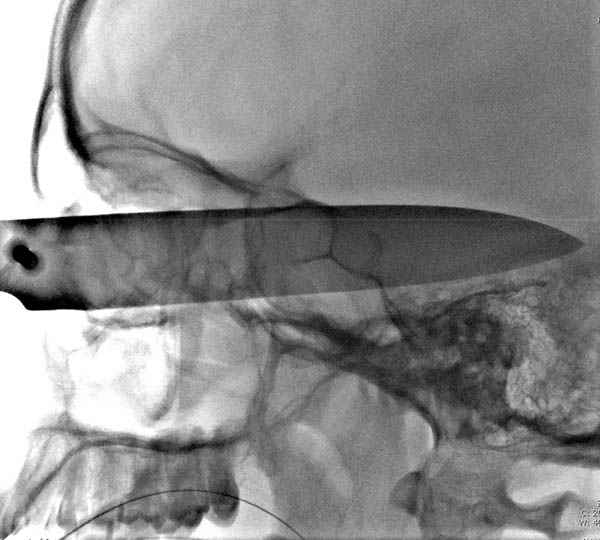

В своих выступлениях я рассказывал, что наши центры в мирное время по пенетрирующим травмам не уступает Ираку или Афганстану, и вот недавно к нам поступила больная 22 лет, травма "ножом в глаз" от бывшей подруги нынешнего "бой френда".

При поступлении в сознании, жаловалась на неприятные ощущения в глазнице.

По протоколу сделаны все необходимые исследования: рентген, ангиограмма с 3Д реконструкцией, где обнаружили что все жизненно важные сосуды не задеты, даже некоторые "сидят" изгибаясь на ноже.

Одним махом нож удалить не удалось, пришлось раскачать и потом двумя руками удалили нож. Рана без кровотечения, обработана и зашита.